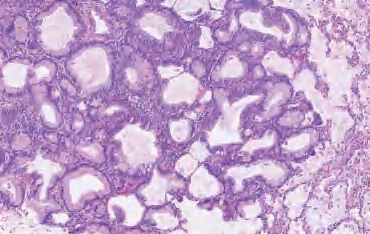

【镜下形态】AAH的细胞为单行排列,细胞间存在间隙,可见钉状细胞和双核细胞,但核分裂象极其罕见(图2-1)。AAH的特点是其增生的细胞依着周围正常的肺泡壁而延续,不像原位癌那样戛然终止。AAH是与鳞状上皮异型增生相对应的一种癌前病变。

图2-1 AAH